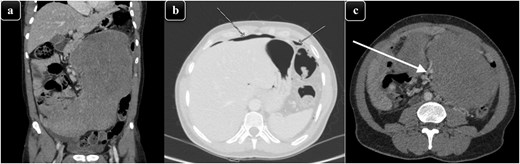

On examination, he looked ill and in pain, was tachycardic with a pulse of 110 bpm, and had a blood pressure of 100/60 mmHg. His abdomen was distended and severely tender with signs of peritonitis, and a huge palpable mass was noted in the entire lower abdomen extending up to the umbilical region. Laboratory tests showed a white cell count of 6.4 (103/μl), C-Reactive protein of 7 mg/l, and lactate of 3.9 mmol/l. A computed tomography (CT) scan of the abdomen and pelvis revealed a large neoplastic mass centered in the abdomen with possible bowel invasion resulting in perforation and pneumoperitoneum, and it was encasing the mesenteric vessels in the lower abdomen (Fig. 1). The radiological differential diagnoses included lymphoma, sarcoma, desmoid, and/or gastrointestinal stromal tumor (GIST).

(a) A coronal view of CT abdomen showing large soft tissue density, homogenously enhancing mass predominantly occupying the left side of the abdomen and reaching to the midline approximately measuring 31 × 19 × 11.7 cm. (b) CT abdomen with an axial view, showing significant pneumoperitoneum. (c) CT abdomen with an axial view showing the mass encasing the mesenteric vessels (white arrow) in the lower abdomen with marked compression and displacement of the adjacent abdominal structures.